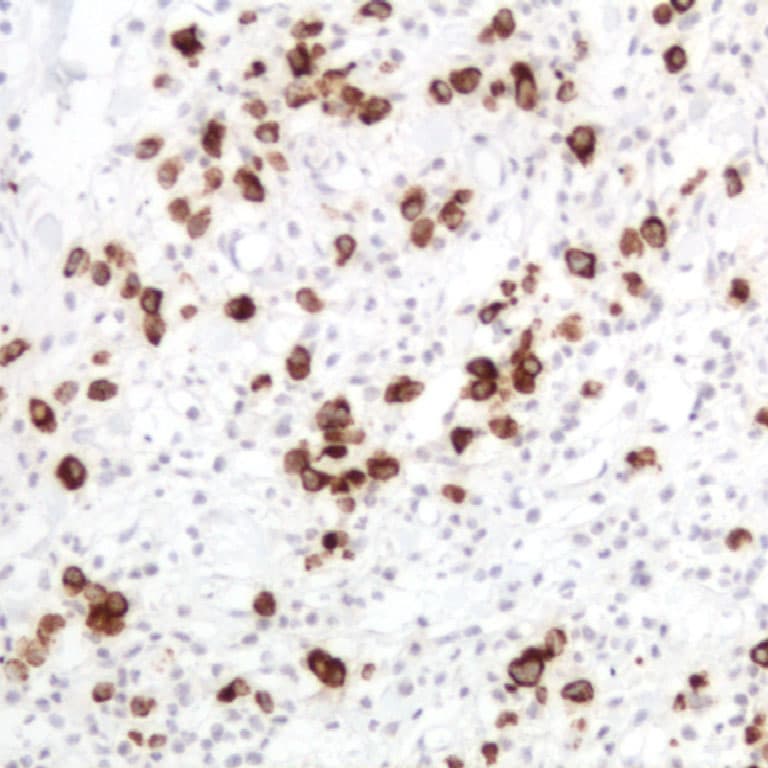

En la práctica clínica, la medición sérica de CA 19-9 es el marcador tumoral más ampliamente validado para el adenocarcinoma ductal de páncreas (PDAC), con sensibilidades agrupadas de alrededor del 79-81 % y especificidades del 82-90 % en pacientes sintomáticos, aunque no se recomienda como herramienta de cribado debido a su limitado valor predictivo positivo. Inmunohistoquímicamente, la detección de CA 19-9 en secciones de tejido fijadas en formalina e incluidas en parafina sirve como complemento diagnóstico en patología gastrointestinal. La tinción IHC para CA 19-9 puede ayudar a confirmar la diferenciación epitelial en adenocarcinomas, particularmente en tumores pancreáticos y biliares donde la positividad citoplasmática es común, y puede incorporarse en paneles IHC junto con marcadores como CK19 y SMAD4 para establecer el origen o subtipo tumoral.

- Alta relación señal-ruido en tejidos tumorales: La IHC Anti-CA 19-9 demuestra consistentemente tinción citoplasmática y asociada a membrana en neoplasias que expresan CA 19-9, facilitando una correlación morfológica precisa con las características histopatológicas.